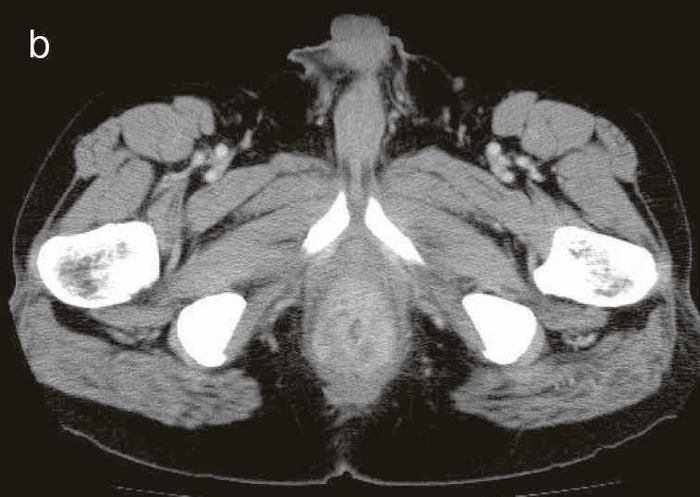

症例3 直腸肛門管癌(60歳代男性)

精査で施行したCT,MRIで痔瘻癌が疑われた。

診断時のMRIでは直腸下部壁内から周囲にhigh intensity areaが拡がり,右側には痔瘻の瘻管を認めた。high intensity areaは前方で前立腺や陰茎海綿体付近まで広がっていた。

CTではMRIと同様に広範囲のhigh density areaがあり,癌と炎症が波及した領域の区別がつかず右側方領域にリンパ節腫大を認めた。